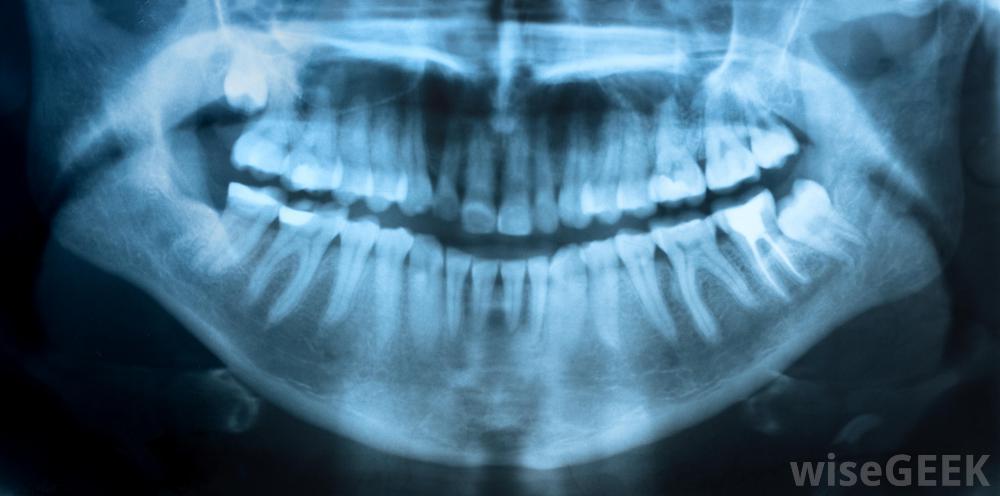

流動牙科包括巡回牙醫,他們去他們需要的地方,而不是讓客戶去他們的辦公室。通常,流動牙醫旅行為低收入的兒童或成人提供牙科護理,或者可能無法獲得此類護理。例如,流動牙科診所可以在學校或健康展覽會上提供醫療服務,也可以前往有疾病的病人家中進行治療,但有時,這些牙醫為那些只需要現場服務的人提供護理,應企業或個人的要求前往提供護理,這些企業或個人有足夠的錢支付牙科診所的電話費。流動牙醫經常攜帶進行牙科x光檢查所需的設備當大多數人需要牙科護理時,他們會去牙醫診所或診所接受治療,一個人可以接受到他所在地的牙科專業人士的護理。這種情況通常被稱為流動牙科。為了確保他們能夠提供所需的護理水平,流動牙醫通常會運送一系列設備和藥物,包括用于麻醉的設備和藥物,到他們打算服務的地方。流動牙醫前往貧困地區,幫助那些通常買不起牙醫的患者通常,流動牙科專業人士旅行的目的是為服務不足的客戶提供護理,例如低收入人群、在合理距離內沒有足夠牙科服務的人以及口腔健康問題風險顯著增加的社區,這些牙醫也為其他類型的客戶服務。例如,公司可以安排流動牙科服務,以確保其員工能夠在現場得到他們需要的護理,而不是錯過重要的工作時間來預約。移動牙科服務也可以設立來在健康活動中提供護理,甚至為那些在家或有足夠錢支付的個人打電話由于高質量的牙科護理需要使用一系列的設備、牙科制劑和藥物,因此流動牙科服務通常乘坐一輛面包車或卡車,并配備了所需的工具提供護理。雖然這種車輛中的設備通常取決于服務計劃提供的護理類型,但這些貨車和卡車通常包括進行牙科檢查、填充空洞、涂抹牙科密封劑、清潔患者牙齒以及修復斷裂或缺口所需的x光設備和工具一些移動牙科車甚至配備了拔牙工具。